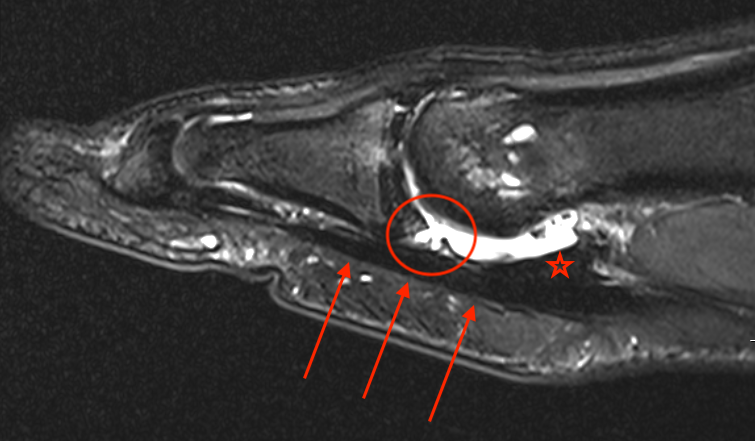

MRI

Sagittal images

Distal avulsion of plantar plate (circle). Star - plantar plate. Arrows - flexor tendon